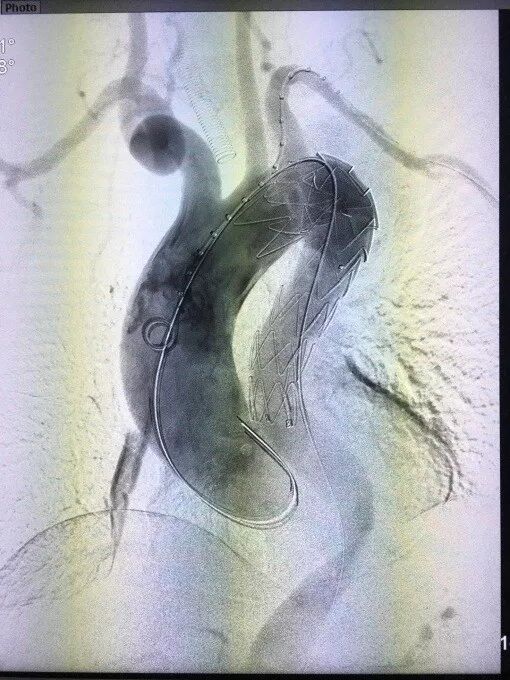

病例2:主动脉夹层,术前造影显示(图2),III型弓,夹层累及左颈总动脉远端,降主动脉迂曲严重;

图2  术前造影-病例2